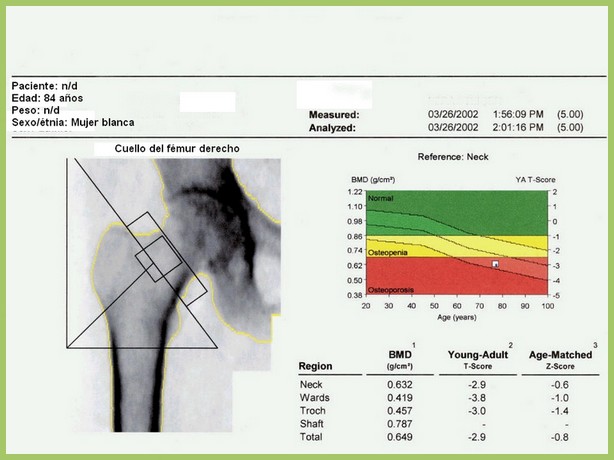

Densitometría ósea: poco cumplimiento de las recomendaciones

06 diciembre 2016

En este estudio argentino, la mitad de las densitometrías se pidieron en mujeres que no cumplían los criterios recomendados de edad o de riesgo aumentado para justificar el rastreo de osteoporosis. Salud Colectiva, octubre de 2016